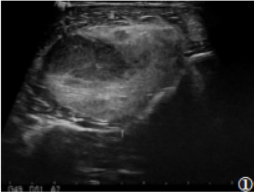

7例均为单发,3例位于大腿,1例位于小腿,1例位于腹膜后,2例位于右侧腰部,肿瘤最大径19.5cm。1例位于腹膜后病灶形态不规则,余6例均为椭圆形病灶。4例行超声检查,表现为边界清楚的团块状稍高回声,形态规则,内回声不均,内可见片状稍低回声(图1)。

图1女,20岁,右胫骨外侧肌肉层内病灶,超声示呈团块状稍高回声,形态规则,内回声不均,内可见片状稍低回声